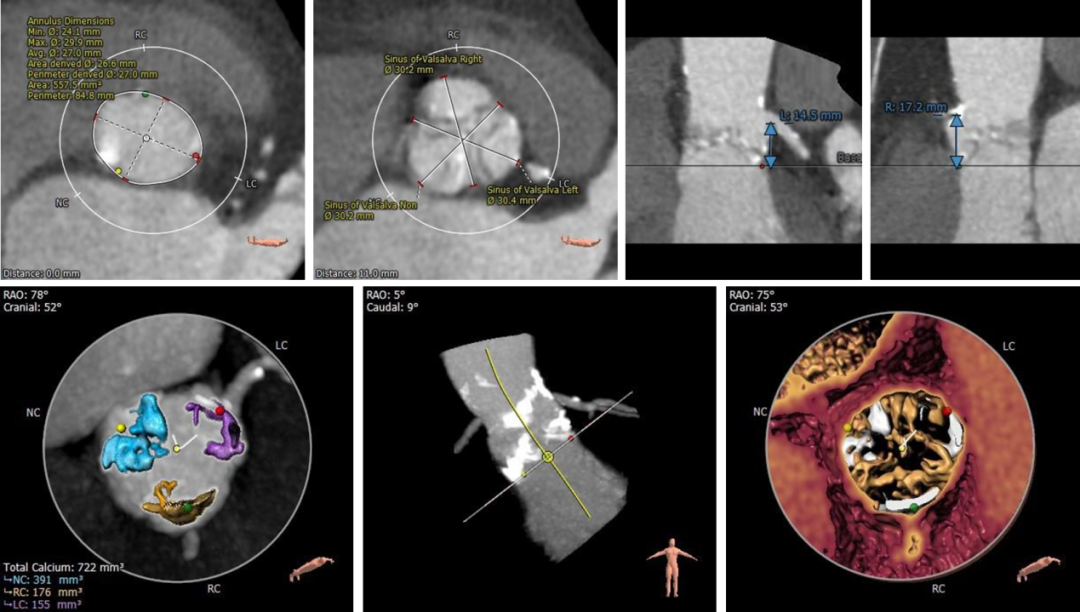

患者为71岁女性,影像学检查提示三叶式主动脉瓣,瓣膜增厚钙化,开放重度受限,钙化积分HU850:722mm³,主动脉瓣口面积仅为0.7 cm²,平均跨瓣压差53 mmHg,主动脉瓣口峰值流速高达4.6 m/s,诊断为主动脉重度狭窄。葛均波院士亲自携多学科团队进行评估并制定了详细的手术方案,拟采用20 mm球囊进行预扩,植入AV26TaurusNXT主动脉瓣。术中通过多次使用回收功能寻找最理想的锚定位置和释放位点,并使用22mm 球囊进行后扩张。术后即刻经食道超声心动图评估显示仅微量瓣周漏,平均跨瓣压差仅为7 mmHg,主动脉瓣口峰值流速为1.9 m/s,术后即刻瓣口面积为2.0cm²,血流动力学指标理想。

主动脉根部及冠脉解剖分析:

血管外周入路评估: